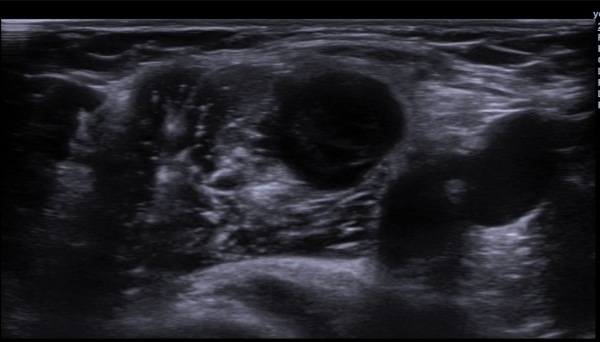

ÃÊÀ½ÆÄ  °Ë»ç  : À­ÆÈ ±ÙÀ§ºÎ Á¤Áß ½Å°æ Ⱦ´Ü¸é°Ë»ç¿¡¼­ Á¤Áß ½Å°æÀÇ ºÎÁ¾°ú ÀϺΠ½Å°æ¼¶À¯ÀÇ Àú¿¡ÄÚ ºÎÁ¾ÀÌ °üÂûµÈ´Ù

(»çÁø 1, 2). ŽÃËÀÚ¸¦ Á¶±Ù ´õ ±ÙÀ§ºÎ·Î À̵¿ÇÏ´Ï Á¤Á߽ŰæÀÇ Àú¿¡ÄÚ ºÎÁ¾ÀÌ °üÂûµÈ´Ù(»çÁø 3, 4).